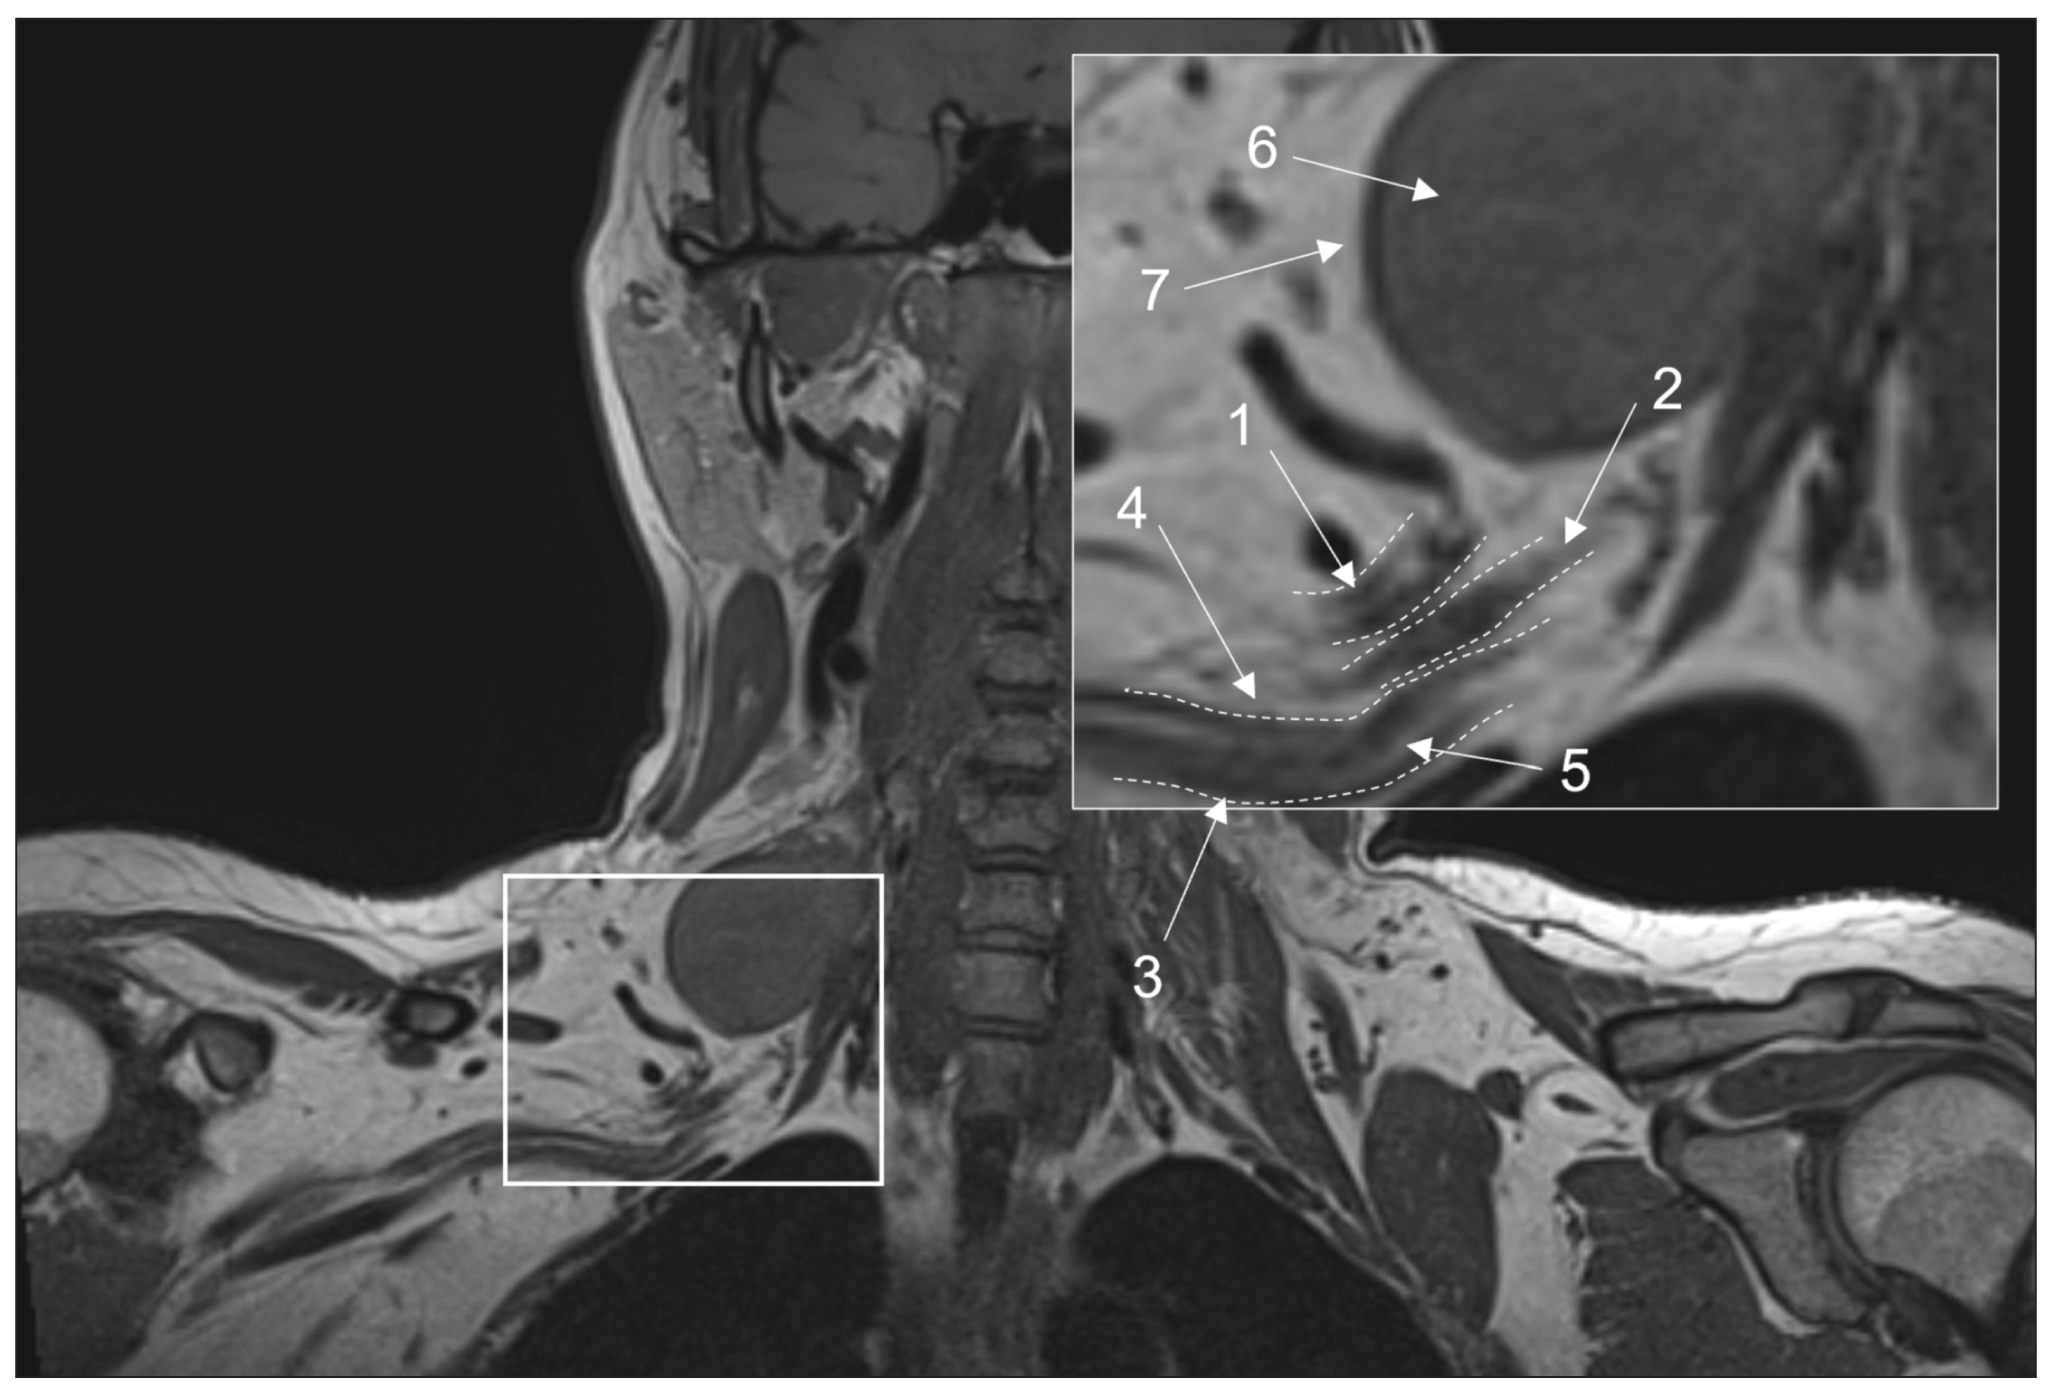

Fig. 1. Magnetic resonance imaging of the brachial plexuses in 3D-T1 mode. A coronal projection: (1) the upper trunk, (2) the middle trunk, (3) the lower trunk, (4) the perineural fatty tissue, (5) the endoneurial fat, (6) a mass lesion (schwannoma), and (7) the intact fatty tissue around the lesion.